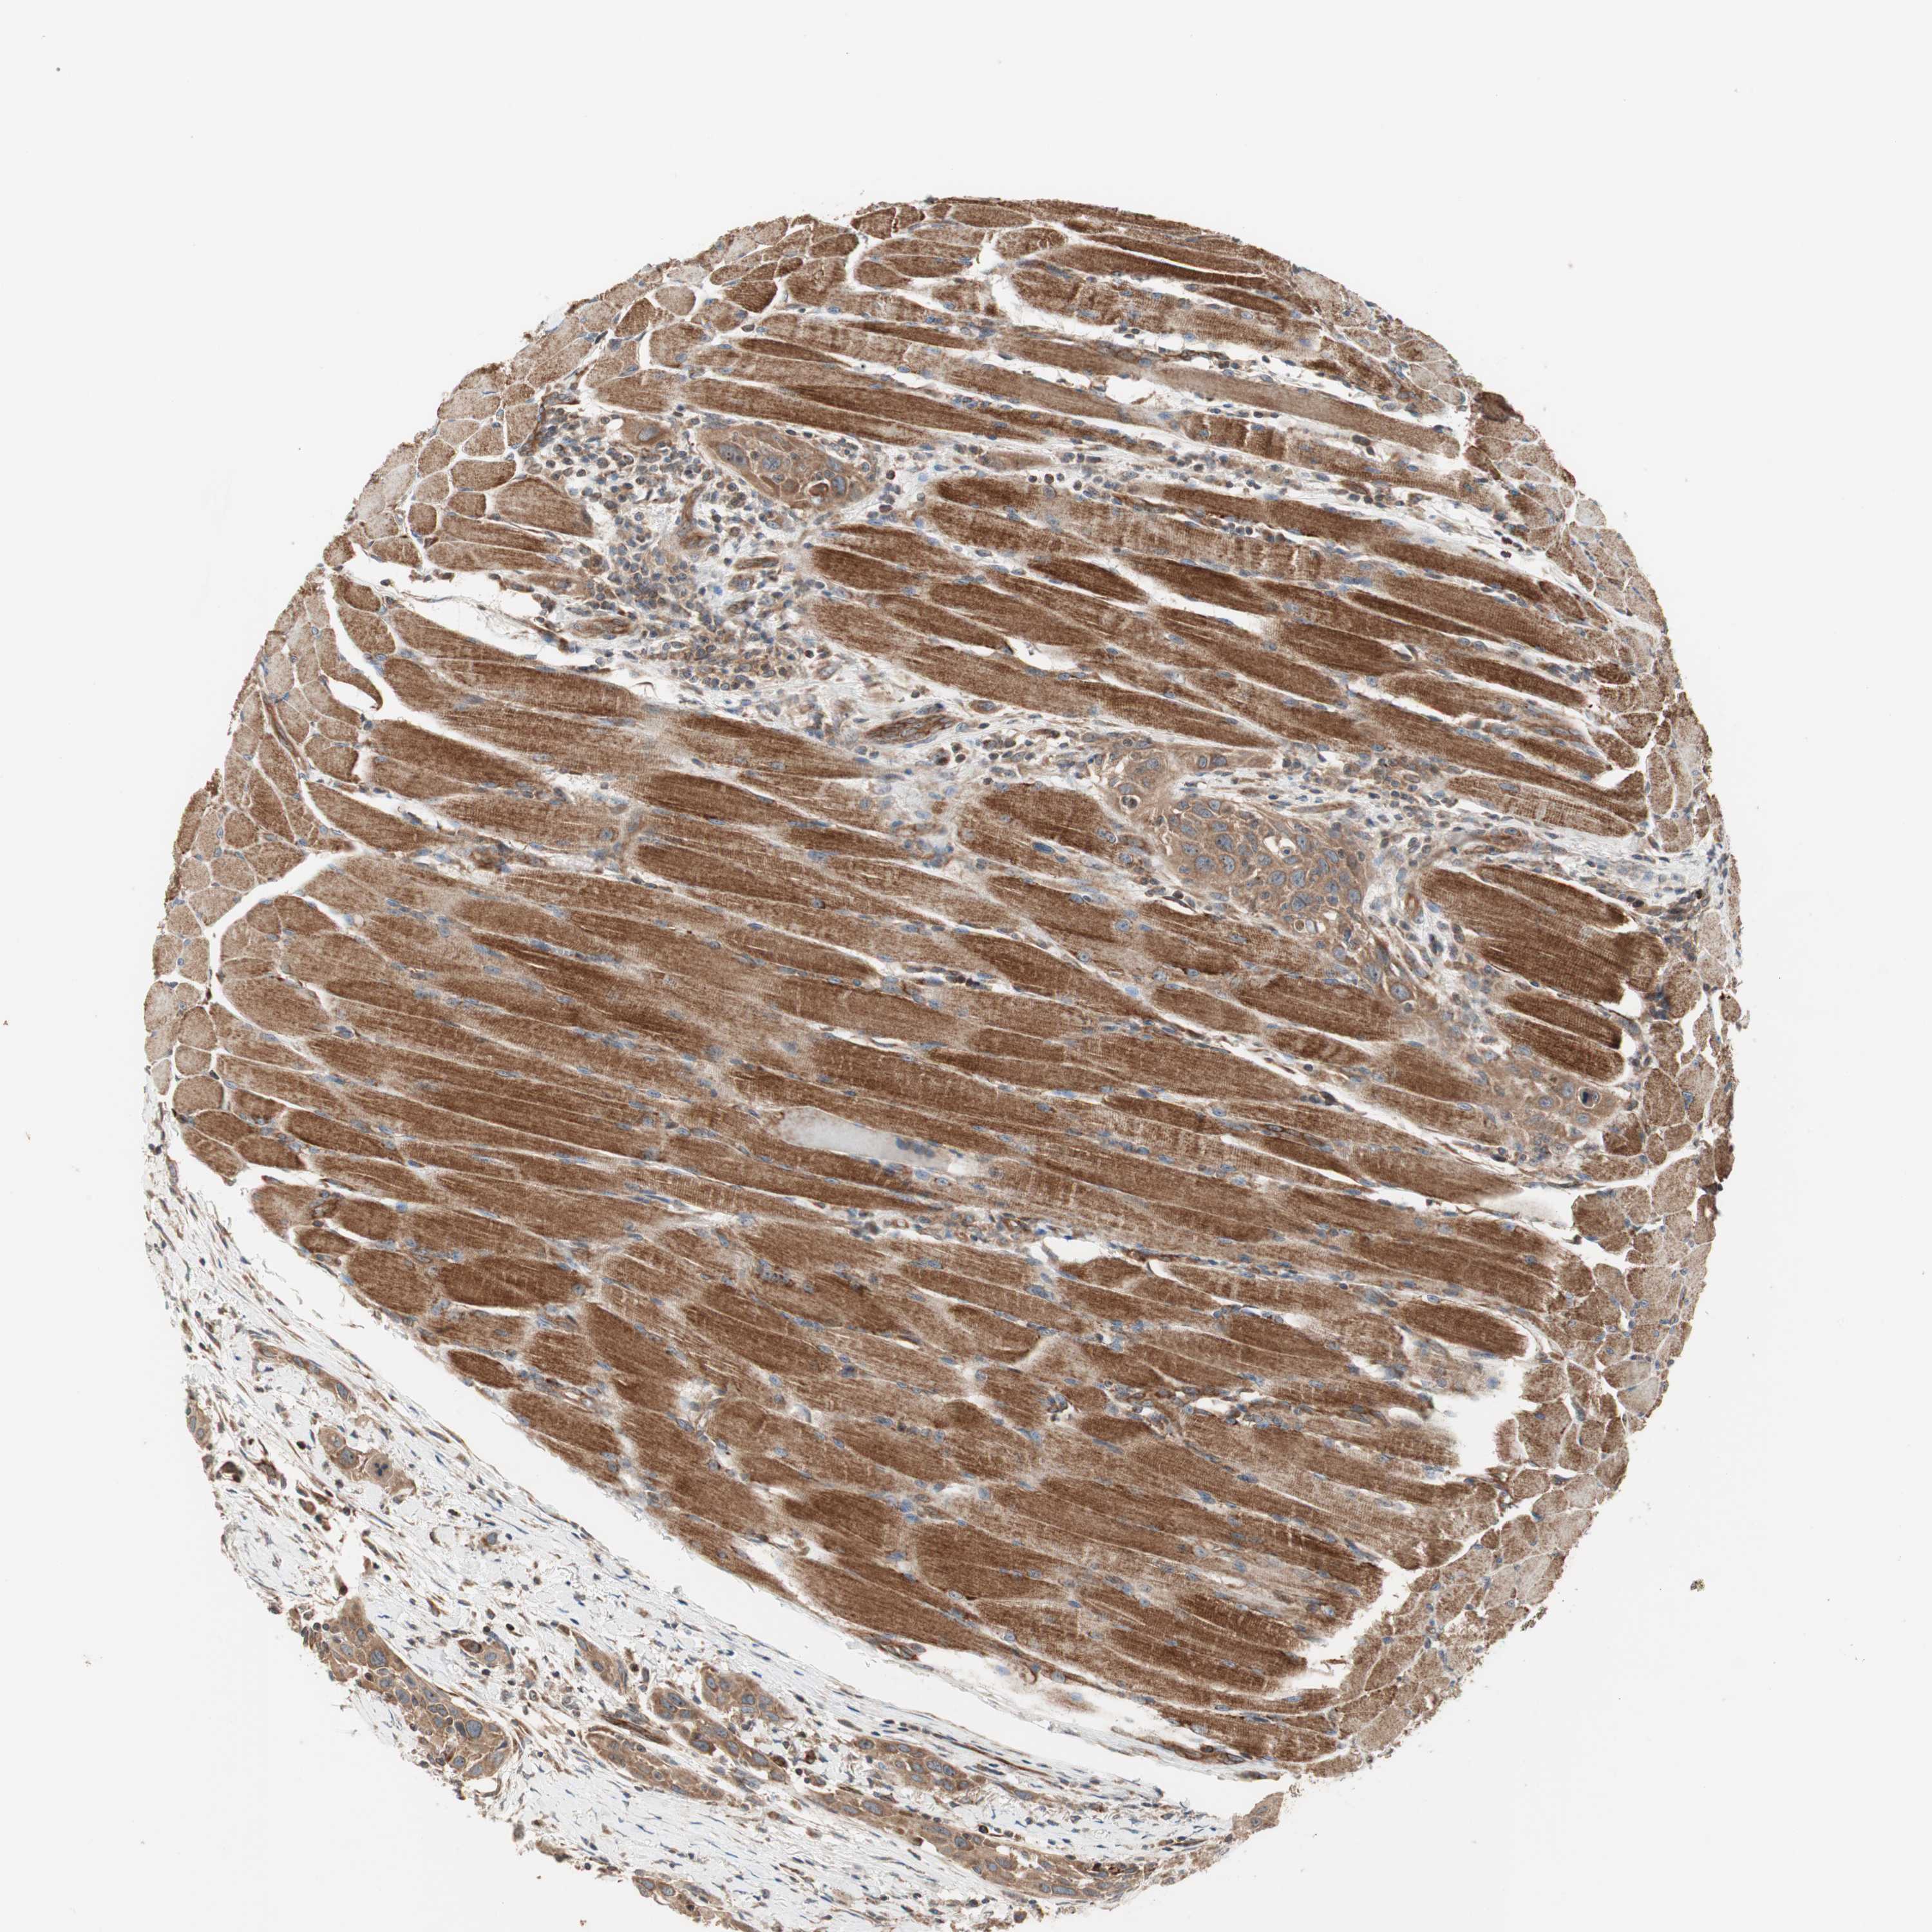

HEAD AND NECK CANCER - Protein expressioni

A mouse-over function shows sample information and annotation data. Click on an image to view it in a full screen mode. Samples can be filtered based on level of antibody staining by selecting one or several of the following categories: high, medium, low and not detected. The assay and annotation is described here.

Antibody stainingi

Antibody staining in the annotated cell types in the current human tissue is reported as not detected, low, medium, or high, based on conventional immunohistochemistry profiling in selected tissues. This score is based on the combination of the staining intensity and fraction of stained cells.

Each image is clickable and will lead to virtual microscopy that enables deeper exploration of all samples and also displays staining intensity scores, fraction scores and subcellular localization as well as patient and tissue information for each sample.

Antibody HPA007301

Staining

High

Medium

Low

Not detected

Intensity

Strong

Moderate

Weak

Negative

Quantity

>75%

75%-25%

<25%

None

Location

Nuclear

Cytoplasmic/membranous

Cytoplasmic/membranous,nuclear

Squamous cell carcinoma, NOS